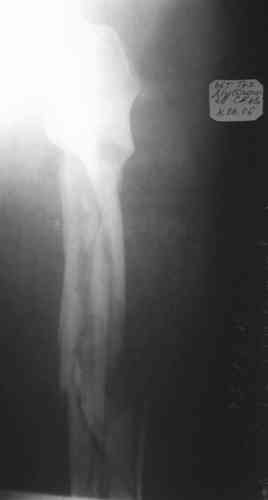

Уважаемые коллеги! Пришел на консультацию вот такой больной (первые 3-и рисунка). Травма автодорожная, апрель 2006г. Лечился консервативно, вытяжение и гипс. Через пять месяцев стал ходить. Укорочение бедра 6 см. 26 февраля 2007г. оступился, упал. Прооперирован в г.Баку - наложен стержневой аппарат. Ходит с костылями, наступая на левую ногу. Мы попросили что нибудь из ранних снимков. Принес рентгенограммы перелома (рис. 4,5). Посмотрели, наснимали сами (рис. 6-10). Похоже, что нет сращения нигде. Хотелось - бы обсудить следующие вопросы:1. дальнейшая тактика - реостеосинтез или подождать (ослабить аппарат, дать нагрузку и т.д.)?2. если реостеосинтез - то чем и как? Юрий Алексеевич Булахтин

Юрий Алексеевич. Привет. А сустав тазобедренный живой? На одном из снимков он возник - но качество рентгенограммы - швах. Если он жживой то я бы сделал

гвоздь с блокированием, через некоторое время после снятия аппрата, вмешиваясь на больших углах малоинвазивно. А если нет.....То стоит подумать

об ТHR с очень длинной ножкой. А Рыков. Хабаровск.